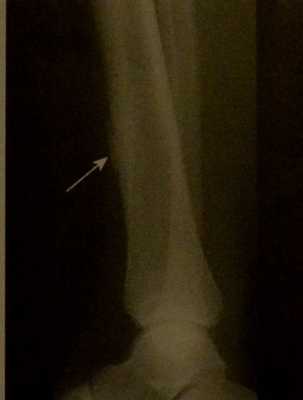

![Снимки МРТ и КТ. Остеосаркома у детей]()

Паростальная остеосаркома. Рентгенограмма большеберцовой кости. Спереди от кости раковиноподобное поражение с узким пространством между опухолью и расположенной рядом костью.